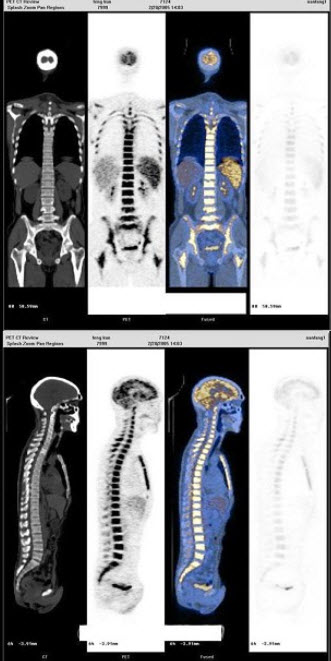

B.PER